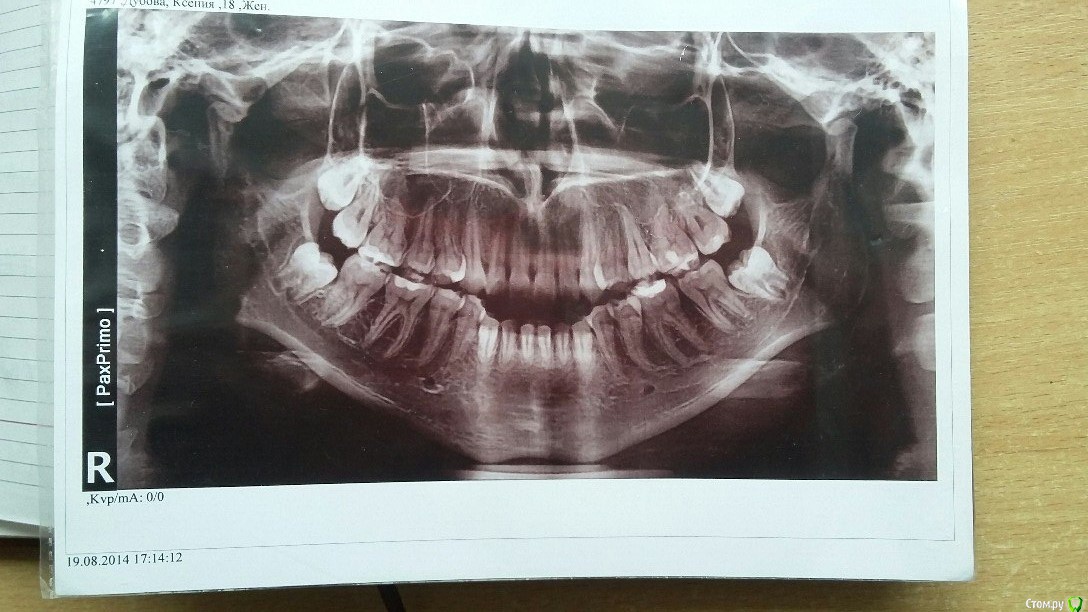

kookai Опубликовано 28 февраля, 2015 Поделиться Опубликовано 28 февраля, 2015 Мне 19 лет. В последние годы стал сильно ухудшаться прикус. Некрасиво, жевать неудобно и т.д.Пошла к одному ортодонту - говорит, такой прикус еще с детства. Нужны брекеты.Все бы ничего, но ортодонт сказал нужно удалять минимум 4 зуба (по-моему четверки). Иначе просто не будет места.Пошла к другому ортодонту - тот наоборот сказал что удалять ничего не надо (разве что зубы мудрости, когда подрастут)Теперь не знаю, что делать. С одной стороны, удалять не хочется, но боюсь носить брекеты, чтоб потом не стало хуже.Возможно ли лечение без удаления четверок, пятерок? Ссылка на комментарий

m.d.n Опубликовано 1 марта, 2015 Поделиться Опубликовано 1 марта, 2015 Нужны специальные снимки. Трг. Клкт. Модели. И конечно грамотный доктор. У вас не самая простая ситуация.тут meaw техника нужна. Ссылка на комментарий